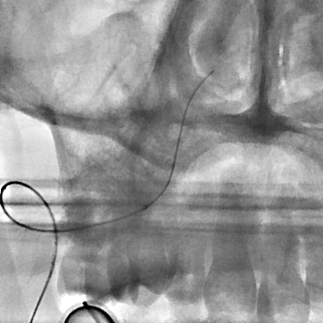

开通这么长节段的夹层所致的椎动脉,说说可以,做起来绝非易事,特别是颅内段,一旦跑到血管外出血,接近脑干,后果严重,谨慎开通的过程还算顺利,微导管带过就是磕磕绊绊不顺利,好吧,小球囊从上到下扩下来,不通,更换稍大球囊扩下来,还是不通,这夹层和狭窄不一样啊,支架导管带过仍然磕磕绊绊,不顺畅,铺开第一个支架,直接来了末端打开不良……,这么长的闭塞段,那得需要多少支架啊?万一放完了,钱花了,不通咋办?

微导管继续超过去,轻轻造影,开通的路径隐约返流闪现,立即改变策略,逆向铺路,开通成功。